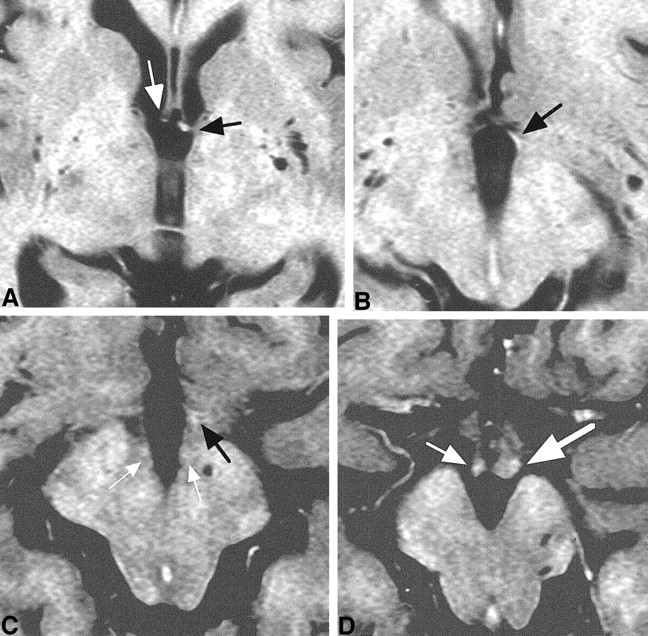

Case 3. Axial T2R images.

A, Fornical column was visible on the left side (black arrow). The right fornical column (white arrow) was decreased in size.

B, Only the left PF (arrow) was visible.

C, PF (black arrow) was visible on the left side only. MT (white arrows) was visible bilaterally.

D, Although bilateral mammillary bodies (arrows) were visible, the right side (small arrow) was decreased in size. The size decrease was compatible with the coronal section (fig 6C).